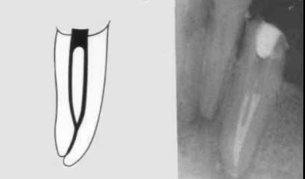

Type 2

(2-1)

Two separate canals leaving the pulp chamber but merging short of the apex to form only one canal